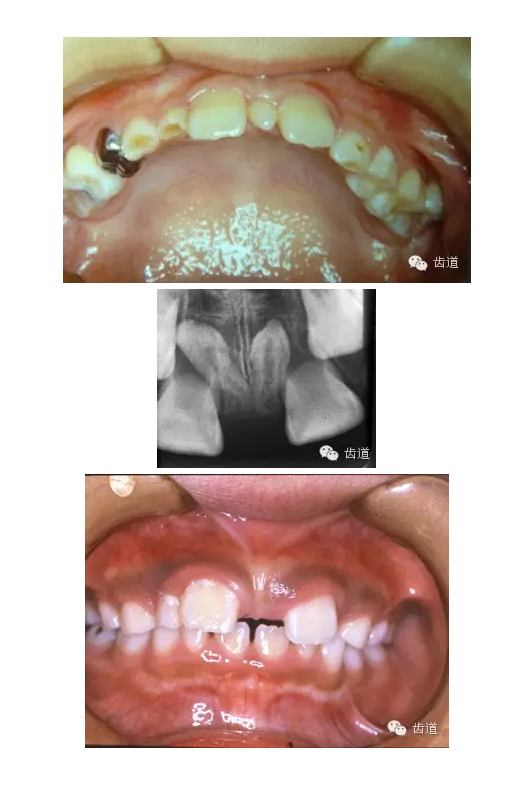

多生牙

超過正常牙數(shù)以外的牙齒

好發(fā)部位:上頜中切牙之間、牙弓末端第三磨牙之后

多呈圓錐形、圓柱形

影響恒牙的發(fā)育和萌出

應(yīng)及時(shí)拔除